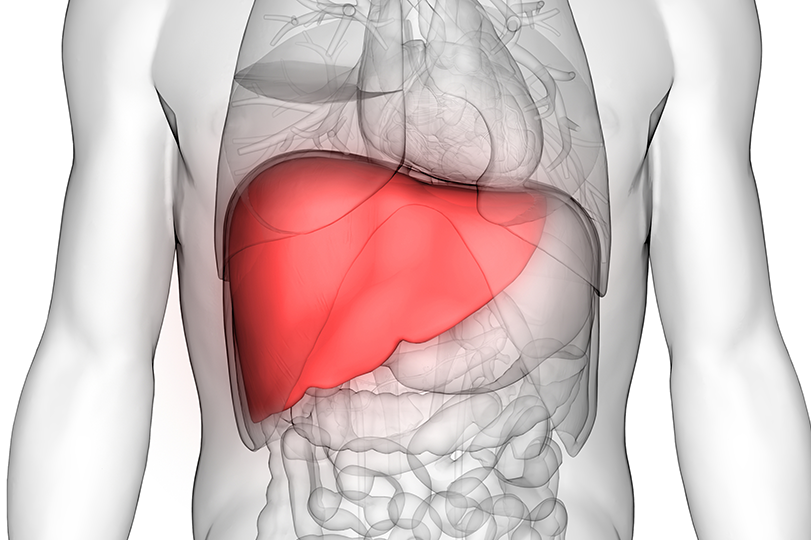

Ficatul este unul dintre cele mai importante organe din corpul nostru. El funcționează ca o „uzină de filtrare”, având rolul de a elimina toxinele, de a metaboliza grăsimile, proteinele și carbohidrații și de a produce bilă, esențială pentru digestie. Atunci când ficatul este suprasolicitat, el devine „încărcat”, iar acest lucru poate afecta întreaga sănătate a organismului.